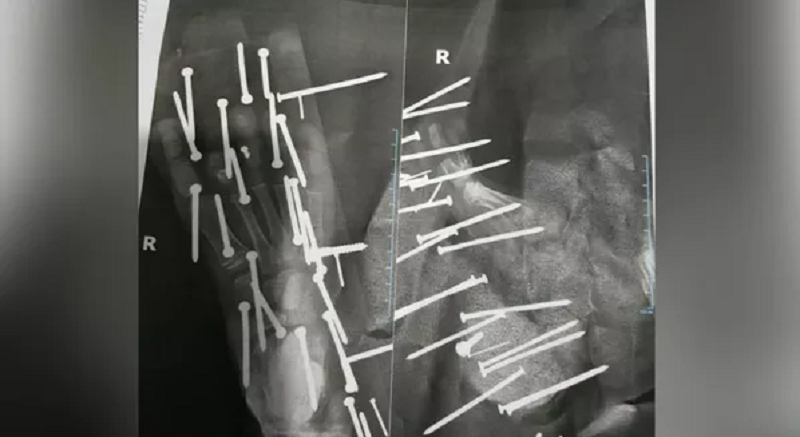

Mais de 28 perfurações foram identificadas no pé da criança — Foto: Reprodução/Redes Sociais

No raio-x que circulou nas redes sociais é possível perceber que o pé do garoto teve no mínimo 28 perfurações de pregos e parafusos. O menino teve que passar por um procedimento cirúrgico.